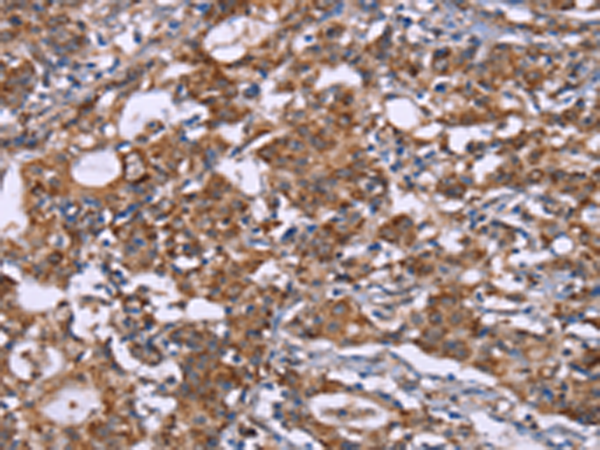

分类: 科研抗体货号: P11835别名: CD50; CDW50; ICAM-R应用: IHC反应种属: Human